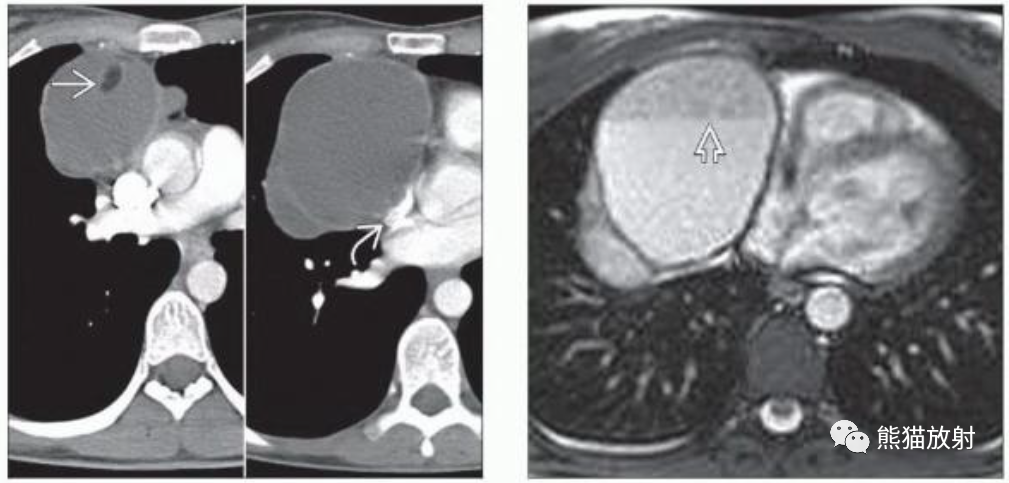

(左)16岁男孩,成熟囊性畸胎瘤,轴位CECT显示右前纵隔肿块,具有软组织、液体和脂肪密度成分。成熟畸胎瘤通常是囊性的,75%可见脂肪密度。

(右)成熟性畸胎瘤的切片显示多个囊性区域(弯箭)与实性软组织成分混合。肿瘤的不均质性导致CT上的特征性表现。

(左) 年轻女性,成熟性畸胎瘤。轴位CT显示右前纵隔多房囊性肿块,上腔静脉受压变扁(弯箭)。虽然病灶以液性密度为主,但局灶性脂肪密度有助于成熟畸胎瘤的诊断。

(右) 轴位T2WI证实了成熟性畸胎瘤的多房囊性表现,并显示了CT上看不到的内部液-液平面。